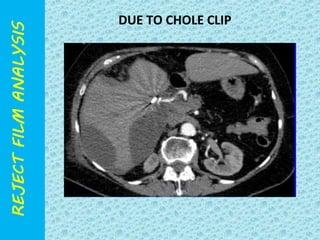

DUE TO CHOLE CLIP